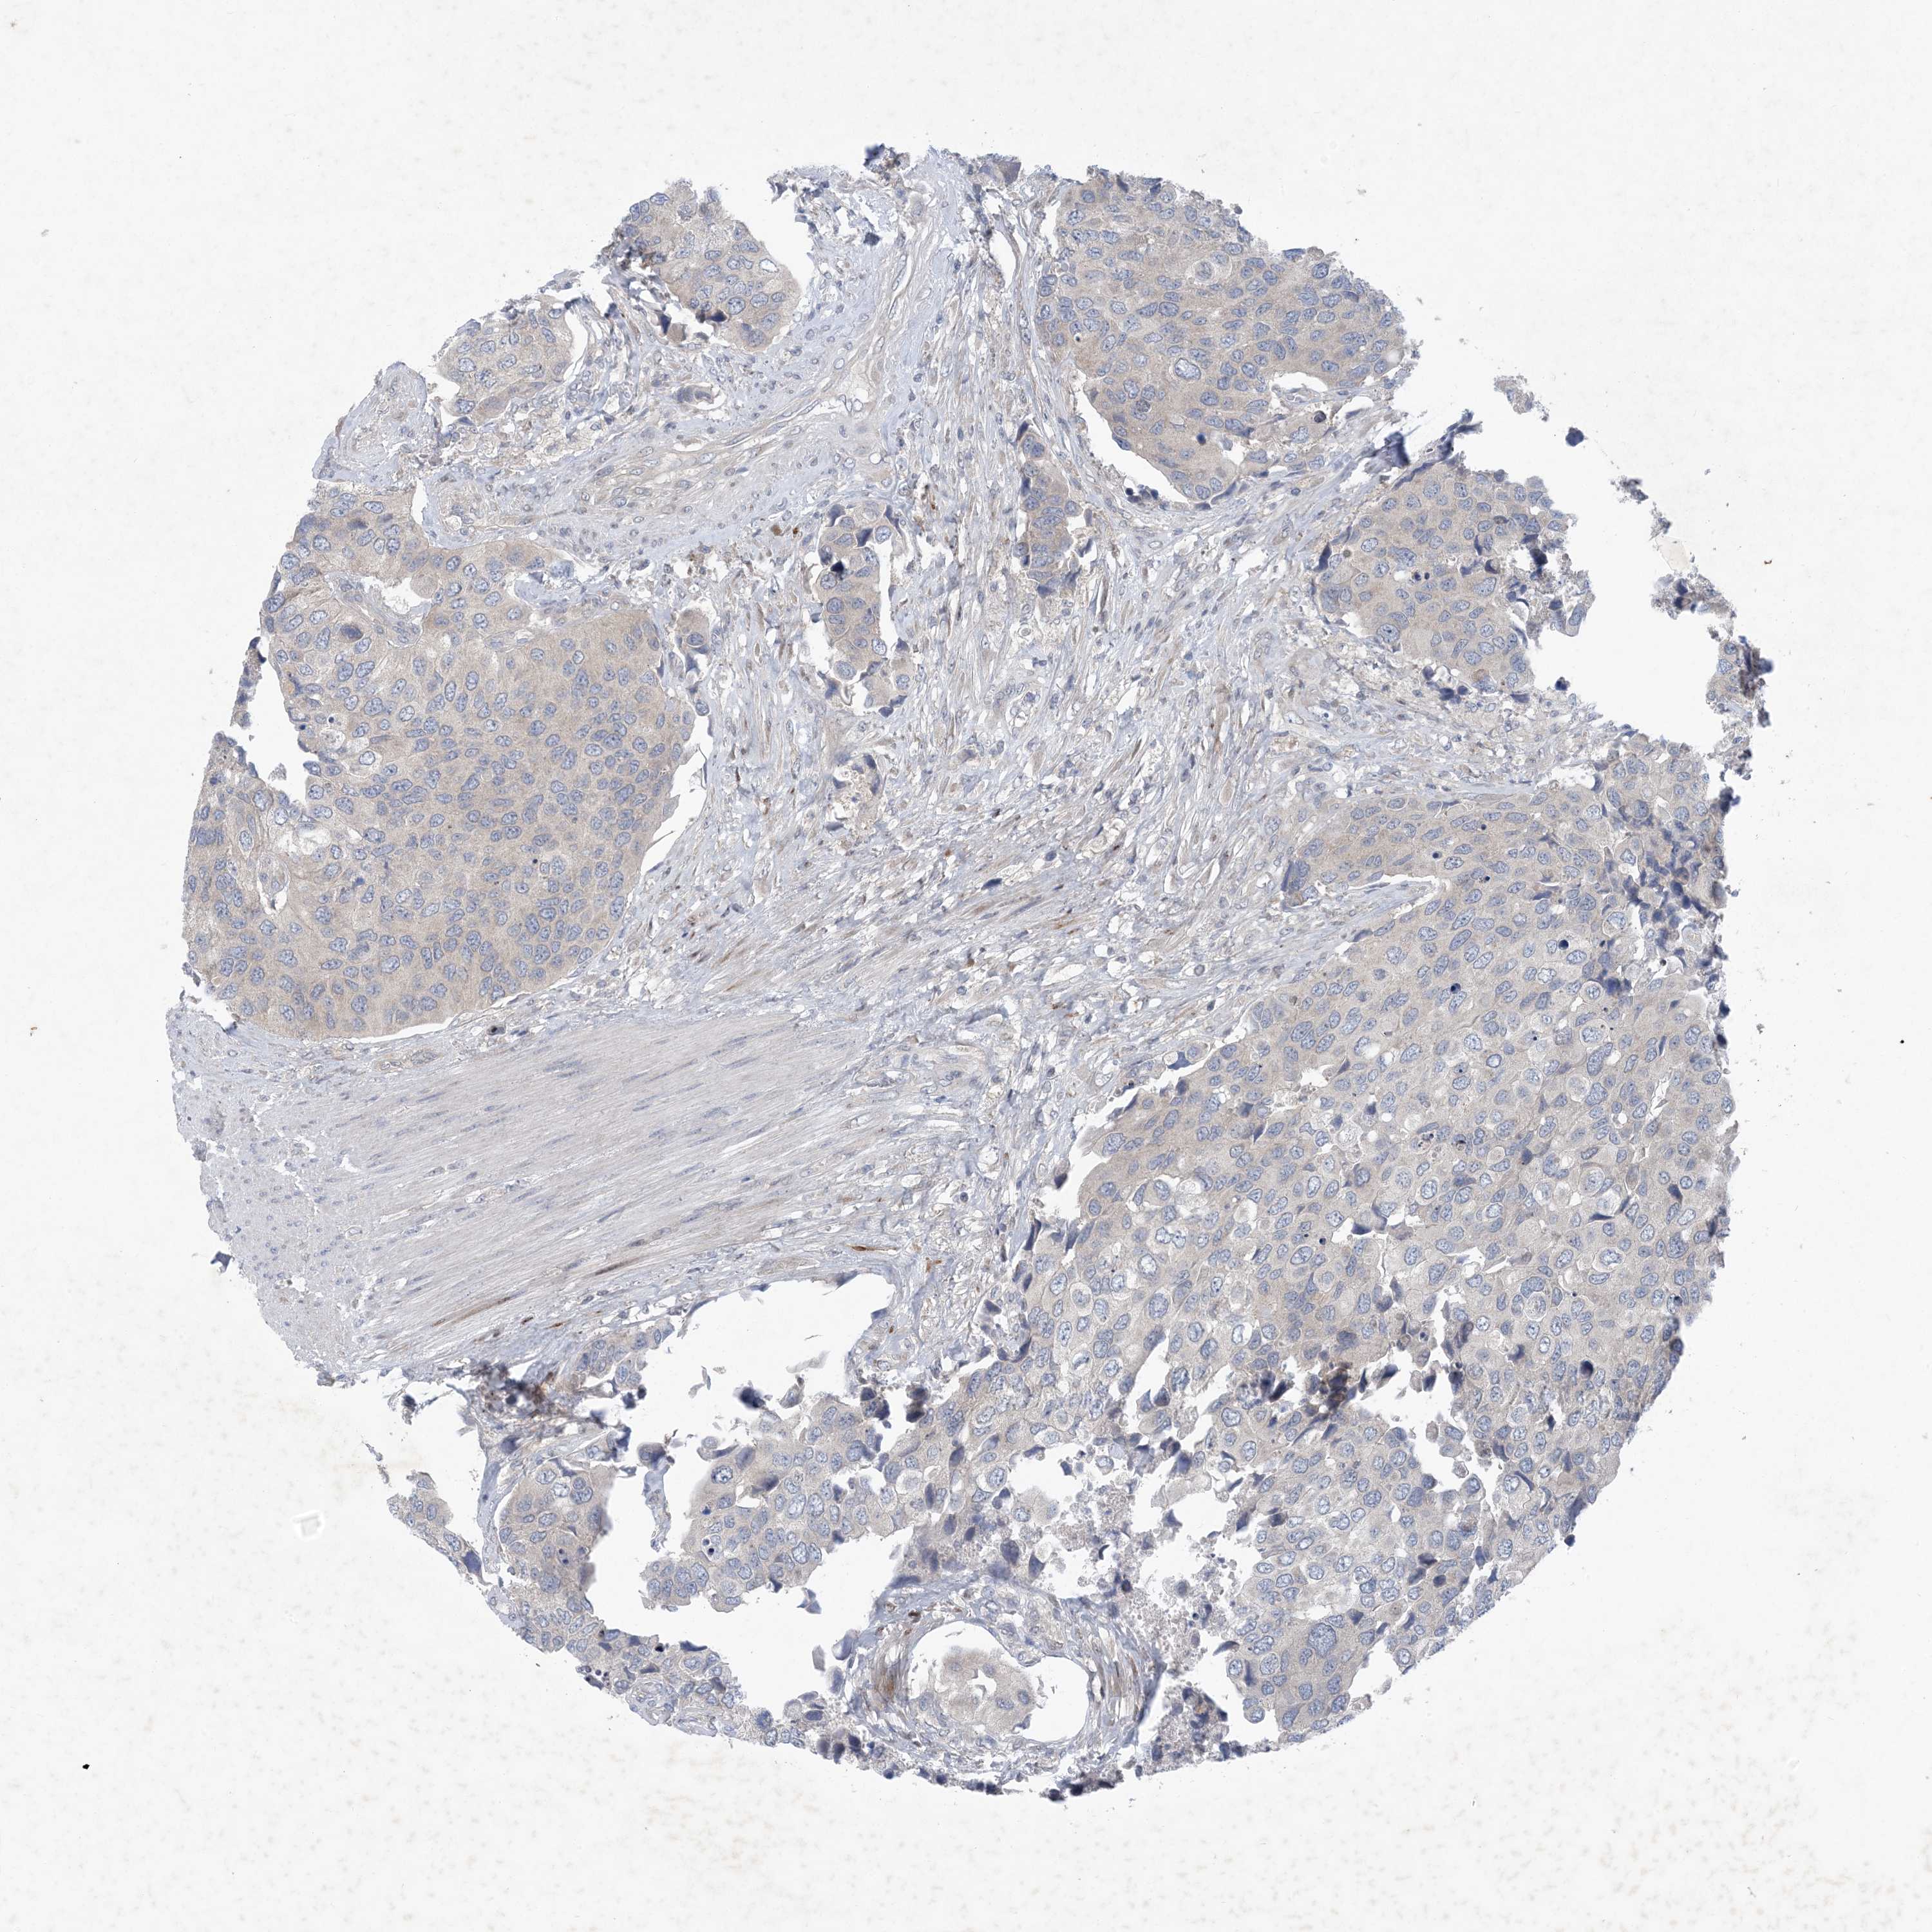

UROTHELIAL CANCER - Protein expressioni

A mouse-over function shows sample information and annotation data. Click on an image to view it in a full screen mode. Samples can be filtered based on level of antibody staining by selecting one or several of the following categories: high, medium, low and not detected. The assay and annotation is described here.

Note that samples used for immunohistochemistry by the Human Protein Atlas do not correspond to samples in the TCGA dataset.

Antibody stainingi

Antibody staining in the annotated cell types in the current human tissue is reported as not detected, low, medium, or high, based on conventional immunohistochemistry profiling in selected tissues. This score is based on the combination of the staining intensity and fraction of stained cells.

Each image is clickable and will lead to virtual microscopy that enables deeper exploration of all samples and also displays staining intensity scores, fraction scores and subcellular localization as well as patient and tissue information for each sample.

Antibody HPA035063

Antibody HPA035064

Urothelial carcinoma, High grade

Urothelial carcinoma, Low grade